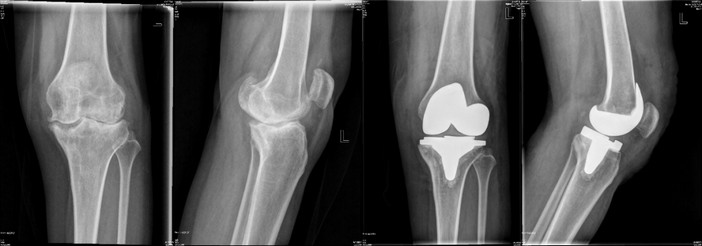

手术治疗

林×,女,51岁,严重膝关节骨关节炎行人工全膝关节置换术,术后6周恢复正常劳动。